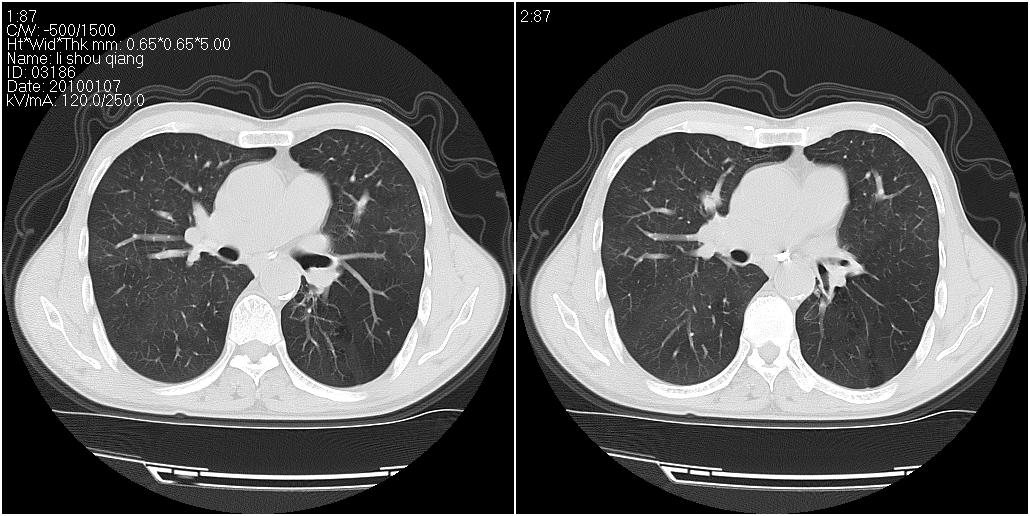

右肺中叶外侧段见一不规则的软组织肿块,边缘可见毛刺,并见厚壁空洞,与胸膜分界欠清。另左下肺见多个小囊状扩张区

1、右肺中叶周围型肺癌并空洞形成。

2、左肺下叶支扩可能性大。

右肺中叶外侧段可见团块影,外形不规则,内见空泡征。左下肺见蜂窝状低密度透亮影,部分层面主动脉旁瘤样突出。考虑右肺中叶外围型肺癌可能性大,左下肺支气管扩张,主动脉弓瘤样突出。

1)考虑右肺中叶周围型肺癌并癌性空洞形成。2)左肺下叶支气管扩张可能性大。

1、右肺中叶周围型肺癌(内空泡)。

2、左肺下叶支扩,不除外合并肺囊肿。